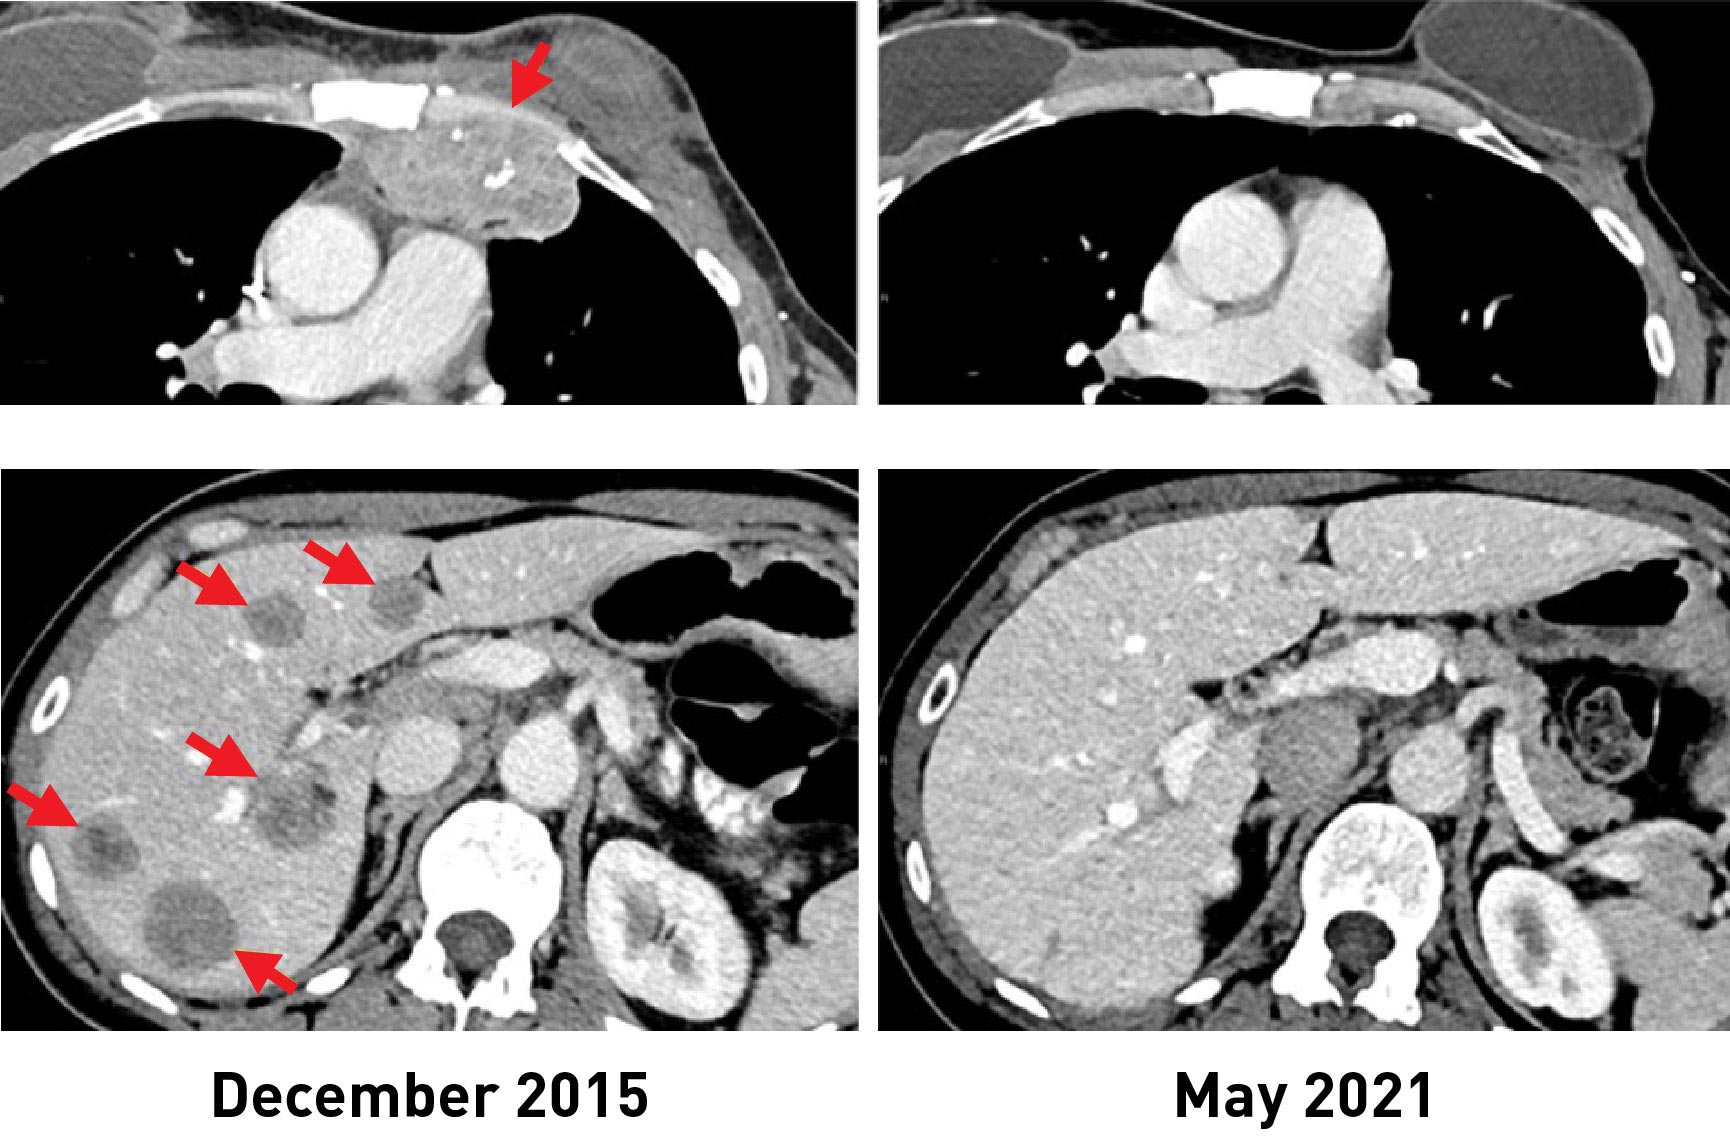

根据美国国立卫生研究院(National Institutes of Health)癌症研究中心(NCI)的研究人员正在进行的一项临床试验的结果,一种利用个人自身抗肿瘤免疫细胞的实验性免疫疗法有可能被用于治疗转移性乳腺癌患者。

在对42名患有转移性乳腺癌的妇女进行的临床试验中,28人(或67%)产生了针对其癌症的免疫反应。该方法被用于治疗6名妇女,其中一半人经历了可测量的肿瘤缩小。试验结果于2022年2月1日出现在《临床肿瘤学杂志》上。

治疗后,这六名妇女中的三人的肿瘤缩小了。其中一位是2018年研究报告中的病例,她至今仍未复发。另外两名妇女在6个月和10个月后,肿瘤分别缩小了52%和69%。然而,一些疾病复发并被手术切除。这些妇女在接受TIL治疗约5年和3.5年后,现在已经找不到罹患癌症的证据。